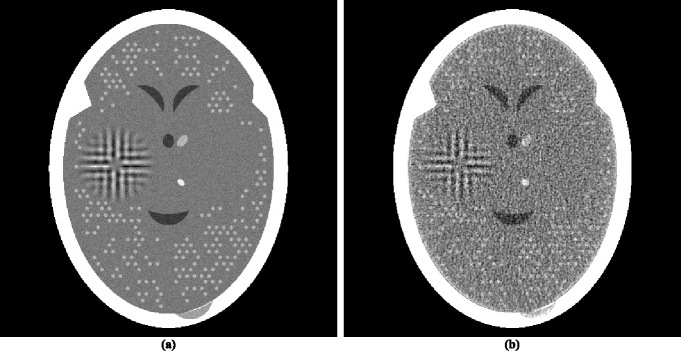

The head phantom that was used for data generation is based on an actual cross-section of the human head. It is described as a collection of geometrical objects (such as ellipses, triangles and segments of circles) whose combination accurately resembles the anatomical features of the actual head cross-section. In addition, the basic phantom contains a large tumor. The actual phantom used was obtained by a random variation of the basic phantom, by incorporating into it local inhomogeneities and small low-contrast tumors at random locations. This phantom is represented by the image in figure 1. That image comprises pixels each of size 0.376 mm by 0.376 mm. The values assigned to the pixels are obtained by an sub-sampling of the pixels and averaging the values assigned to the sub-samples by the geometrical objects that are used to describe the anatomical features and the tumors. Those values are approximate linear attenuation coefficients per cm at 60 keV (0.416 for bone, 0.210 for brain, 0.207 for cerebrospinal fluid). The contrast of the small tumors with their background is 0.003 cm-1. In order to clearly see the low-contrast details in the interior of the skull, we use zero (black) to represent the value 0.204 (or anything less) and 255 (white) to represent 0.21675 or anything more).

For the selected head phantom we generated parallel projection data, in which one view comprises estimates of integrals through the phantom for a set of 693 equally-spaced parallel lines with a spacing of 0.0376 cm between them. (We chose to simulate parallel rather than divergent projection data, since the reconstruction by the method ofSIDK08a (42) with which we wish to compare the superiorization approach were performed for us by the authors ofSIDK08a (42) on parallel data. Even though contemporary CT scanners use divergent projection data, results obtained by the use of parallel projection data are relevant to them, since it is known that the quality of reconstructions from these two modes of data collection are very similar as long as the data generations use similar frequencies of sampling of lines and similar noise characteristics in the estimated integrals for those lines; see, for example, the reconstructions from divergent and parallel projection data in figure 5.15 of HERM09a (55).) In calculating these estimates we take into consideration the effects of photon statistics, detector width and scatter. Details of how we do this exactly can be found in Sections 5.5 and 5.9 of HERM09a (55). Briefly, quantum noise is calculated based on the assumption that approximately 2,000,000 photons enter the head along each ray, detector width is simulated by using 11 sub-rays along each of which the attenuation is calculated independently and then combined at the detector, and 5% of the photons get counted not by the detector for the ray in question but detectors for the neighboring rays. For the experiments in this paper, we did not simulate the poly-energetic nature of the x-ray source. To indicate what can be achieved in clinical CT, we show in figure 1(b) a reconstruction that was made from data comprising of 360 such views with the reconstruction algorithm known as ART with blob basis functions; see(HERM09a, 55, Chapter 11).

There have appeared in the literature some approaches to minimization that seem to indicate a more efficacious performance for CT than the one reported in HERM08a (31). One of these is the Adaptive Steepest Descent Projections Onto Convex Sets (ASD-POCS) algorithm, which is described in detail in the much-cited paper of Sidky and PanSIDK08a (42) and whose use has been since reported in a number of subsequent publications, for example, in SIDK11a (23, 43). We note that ASD-POCS was designed with the aim of producing an exact minimization algorithm, in contrast to our heuristic superiorization approach. Translating equations (6)-(8) of SIDK08a (42) into our terminology, the aim of ASD-POCS is the following: Given an , find an -compatible for which is minimal. (Note that this aim is a special case of the constrained optimization formulation presented in (10).) In order to test ASD-POCS, we generated realistic projection data as described in the previous subsection but for only 60 views at 3 degree increments with the spacing between the lines for which integrals are estimated set at 0.752 mm. Thus the number of rays (and hence the number photons put into the head) in this data set is a twelfth of what it is in the data set used to produce the reconstruction in figure 1(b). A reconstruction from these data was produced for us using ASD-POCS by the authors of SIDK08a (42) (this ensured that it does not suffer due to our misinterpretation of the algorithm or from our inappropriate choices of the free parameters), it is shown in figure 2(a).

Since the image quality of figure 2(a) is not anywhere near to that of figure 1(b), we present here a brief discussion as to why we are showing such images. Many publications in the recent medical imaging literature have claimed that medically-efficacious reconstructions can be obtained by the use of -minimization from data as sparse as what was used to produce figure 2(a). (In fact, ASD-POCS was motivated and used with such an aim in mindSIDK11a (23, 42, 43).) Such publications usually show reconstructions from sparse data as evidence for the validity of their claims. They can do this because in their presented illustrations the features that are observable in the reconstructions are usually much larger and/or of much higher contrast against their backgrounds than the small “tumors” in figure 1(a), which are perfectly visible in the reconstruction in figure 1(b), but are not detectable in the reconstruction from sparse data in figure 2(a). The reason why that reconstruction appears to be unacceptably bad is that the display window (from 0.204 cm-1 linear attenuation coefficient to 0.21675 cm-1 linear attenuation coefficient) is very narrow; it was selected to enhance the visibility of the small low-contrast tumors. The width of this window corresponds to about 13.5 Hounsfield Units (HU). As compared to this, in their evaluation of sparse-view reconstruction from flat-panel-detector cone-beam CT, Bian et al.BIAN10A (43) use what they call a “soft-tissue grayscale window” (also a “narrow window”) from -429 HU to 429 HU to display head phantom reconstructions. Using such a window for our reconstructions shown figures 2(a) and 1(b) would result in images that are nearly indistinguishable from each other. Thus reporting the images using such a display window is consistent with the claim that a TV-minimizing reconstruction from a few views is similar in quality to a more traditional reconstruction from many views. However, our much narrower display window reveals that this is not really so. We therefore continue using our much narrower window in what follows, since it clearly reveals the nature of the reconstructions being compared, warts and all.